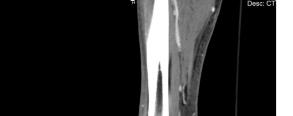

The patient’s initial laboratory studies are demonstrated in Table 1. The patient had radiographs taken of the bilateral lower extremities as well as a computed tomography (CT) of the right lower extremity. Radiology reads of the radiographs showed “postsurgical changes of both left and right fibular shaft resections with scattered surgical clips. No evidence of osteomyelitis. No acute fractures or dislocations. No evidence of subcutaneous gas.” Result of the CT of the right lower extremity demonstrated “extensive subcutaneous fat stranding, skin thickening with ulcerations consistent with cellulitis (Image 3). No rim-enhancing fluid collections to suggest an abscess. No evidence of soft tissue gas. Post-surgical changes of distal fibular shaft resection and multiple surgical clips. No significant osseous erosions or periosteal reaction.” The patient was given empiric antibiotic coverage with vancomycin and piperacillin-tazobactam due to concern for infection. He was given IV fluids, and morphine for pain control. He was admitted to the family medicine service where a diagnostic test was ordered, and the diagnosis was made.

Image 1. Photographs of a 45-year-old male with lower extremity wounds, swelling, and a rash. A) Bilateral lower extremities showing an erythematous, papular, non-blanching rash present from the anterior thighs to the feet. B) Right ankle ulcer with a membranous covering (white arrow) and wound with eschar (black arrow). Image 2. Photograph of an ulcer with membranous covering (white arrow) on the anterolateral right ankle of a 45-year-old male who presented with lower extremity wounds, swelling, and a rash. Image 3. Computed tomography sagittal view of the distal right lower extremity of a 45-year-old male with lower extremity wounds, swelling, and a rash.